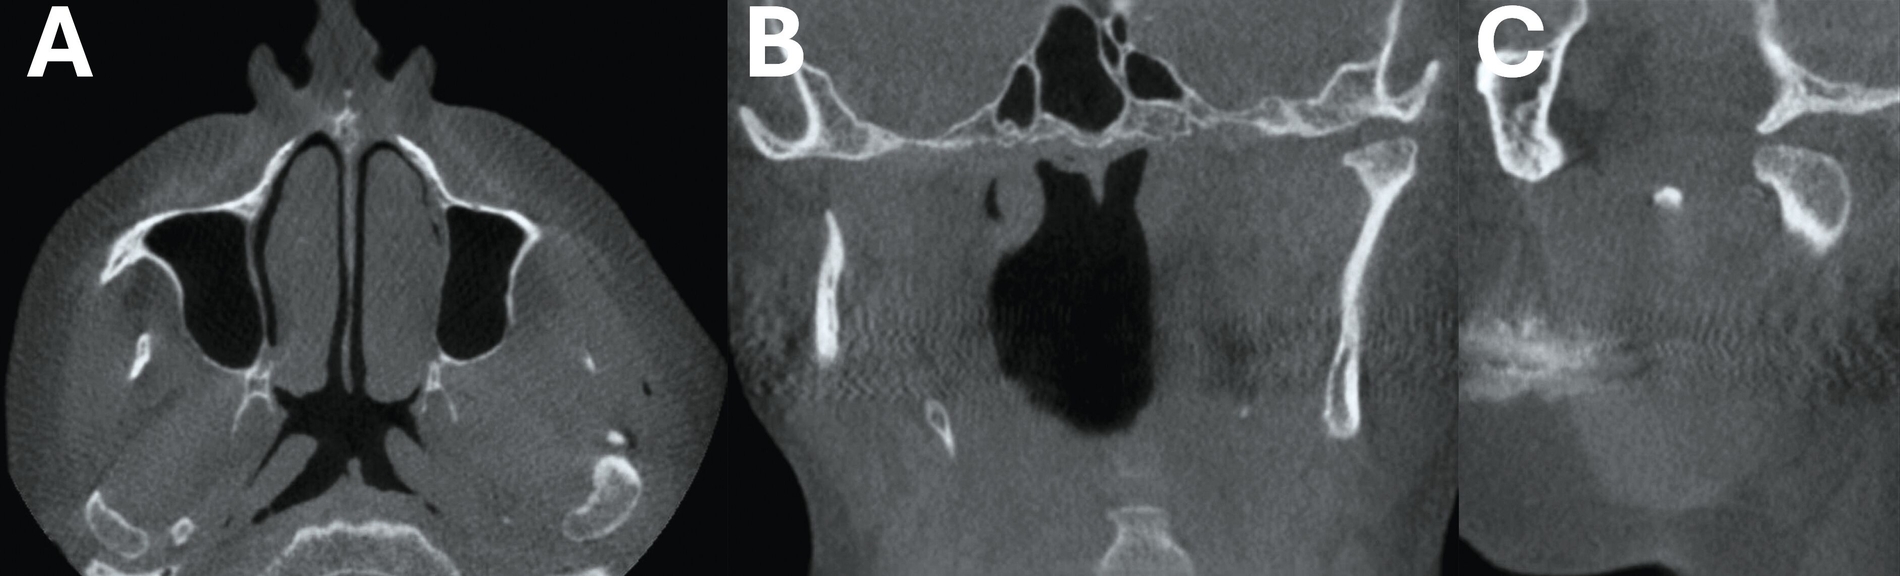

In Anbetracht des klinische Befunds wurde eine Computertomografie des Gesichtsschädels durchgeführt, die eine hochgradige Kiefergelenkarthrose links offenbarte. In den Bildern erkennbar ist allerdings eine ausgeprägte Ummauerung des originären Caput mandibulae mit knochendichter Struktur und freien Gelenkkörpern (Abbildung 7).